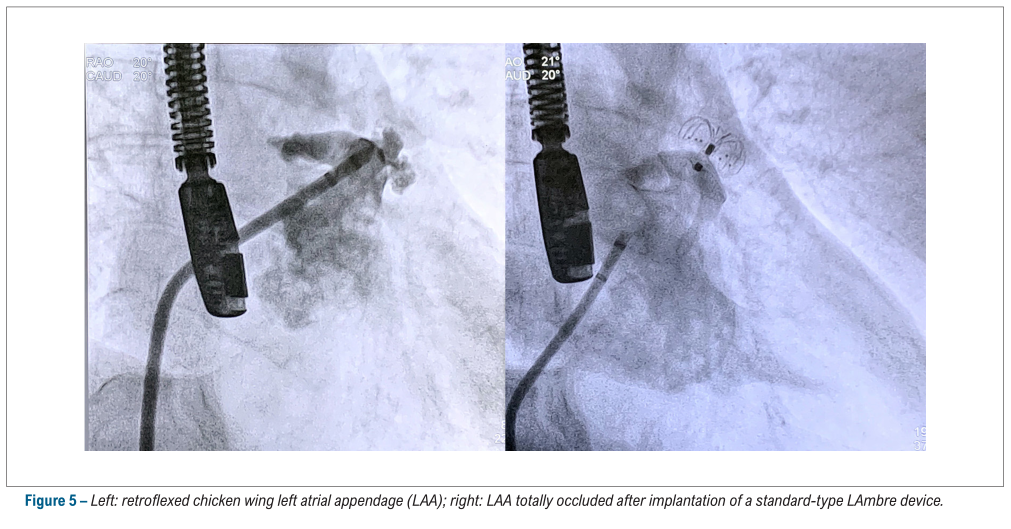

LAmbre™术中影像